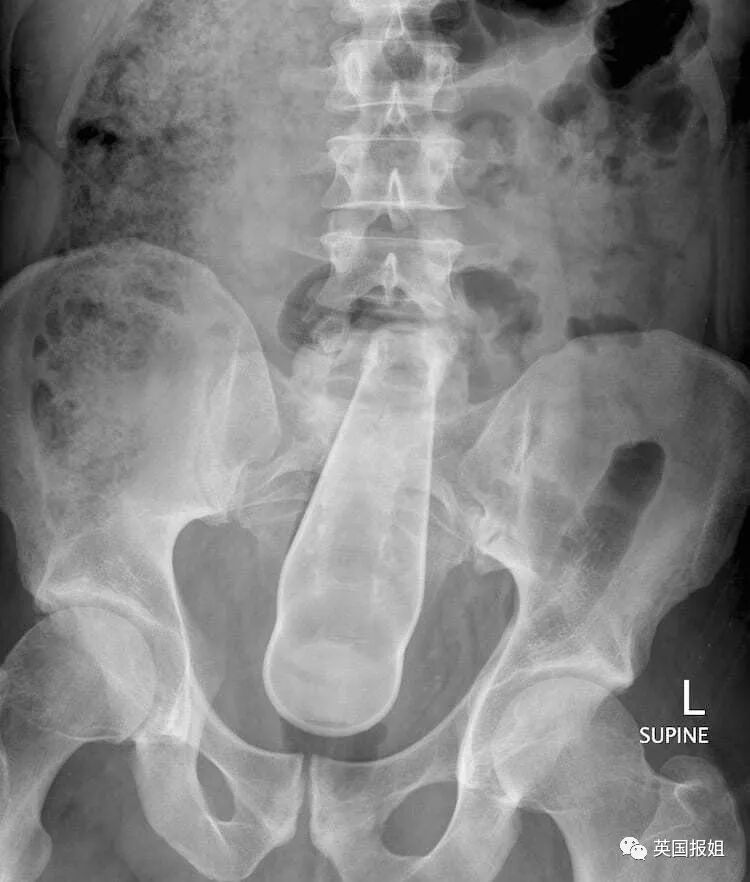

但最近有个走私犯不走寻常路,他把金条藏进了屁股里…

价值4.6万英镑的2磅(约2斤重)黄金都塞进去了,如果大家对2斤重的黄金到底有多少没啥概念,

这是海关人员拿出来的金子照片。

据说,当时这名男子是因为在机场走路姿势非常诡异,所以被工作人员拦下来进行了检查,这才发现了黄金。